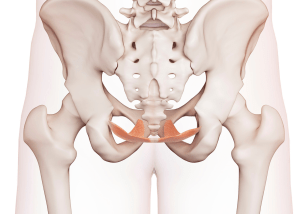

Breathing plays a large role in the interaction between pelvic floor, abdominals and diaphragm; this will also have an effect on continence and respiration. Contraction and relaxation of the diaphragm is affected by the contraction of the abdominals which if occurring simultaneously increases intra-abdominal pressure, thus trunk stability can be increased with simultaneous contraction of the diaphragm and abdominals. The pelvic floor does not independently contract itself but reacts and controls changes in intra-abdominal pressure by working with the diaphragm and abdominals, relaxing briefly on inspiration to allows downward movement of the diaphragm then co contracting with the abdominals during exhalation and coughing allowing upward movement of the diaphragm by increase IAP. Thus, providing active support through constant contraction while passive support of the pelvic occurs through form closure of the sacroiliac joint or SIJ. Force closure of the pelvis refers to interlocking of the joint surfaces, whereas form closure is through compressive forces of the muscles, ligaments, fascia and provides passive stability. Therefore, patients with DRAMS and a weakened linea alba, have poor form closure when performing a curl up task highlighting reduced IAP, reduced trunk mechanics and pelvic instability due to the lack of muscular passive support.

Breathing plays a large role in the interaction between pelvic floor, abdominals and diaphragm; this will also have an effect on continence and respiration. Contraction and relaxation of the diaphragm is affected by the contraction of the abdominals which if occurring simultaneously increases intra-abdominal pressure, thus trunk stability can be increased with simultaneous contraction of the diaphragm and abdominals. The pelvic floor does not independently contract itself but reacts and controls changes in intra-abdominal pressure by working with the diaphragm and abdominals, relaxing briefly on inspiration to allows downward movement of the diaphragm then co contracting with the abdominals during exhalation and coughing allowing upward movement of the diaphragm by increase IAP. Thus, providing active support through constant contraction while passive support of the pelvic occurs through form closure of the sacroiliac joint or SIJ. Force closure of the pelvis refers to interlocking of the joint surfaces, whereas form closure is through compressive forces of the muscles, ligaments, fascia and provides passive stability. Therefore, patients with DRAMS and a weakened linea alba, have poor form closure when performing a curl up task highlighting reduced IAP, reduced trunk mechanics and pelvic instability due to the lack of muscular passive support.